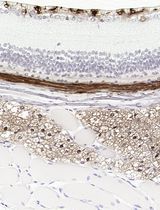

Chemoresistance is one of the special properties of cancer stem cells, which is the main cause of chemotherapy failure and plays an important role in the recurrence of various cancers including osteosarcoma. The most widely used assay for evaluating chemoresistance is the modified cell proliferation assay. An equal number of cells are seeded onto 96-well culture plates or 24-well plates, and then different concentrations of anti-cancer drugs are added into each well. After that, measure the cell density or cell activity to observe the effect of anti-cancer drugs to cancer cells or cancer stem cells. The chemoresistance of cells is stronger, the cell density or cell activity is higher. Here, we describe chemosensitivity assays for osteosarcoma cells and osteosarcoma stem-like cells.